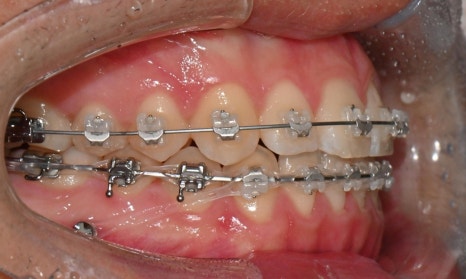

2024.12. 초진 구내사진 - 연세정원치과

정밀 검진 결과, 하악 치열이 좌측으로 틀어져 있었고 그로 인해 위아래 치아 중심선이 일치하지 않았습니다. 아래 치열이 전체적으로 전방 위치하여 아래 입술 돌출이 더 도드라져 보이는 상태였습니다. 그리고 상악궁이 하악궁보다 좁아서 앞니 부위 일부 반대로 물리는 치아 교합도 관찰되었습니다. 특히 외상 치아의 경우, 교정력 적용시 추가적인 염증성 치근 흡수 위험이 존재하기 때문에, 치료 중 지속적인 관찰이 필수적인 상황이었습니다.